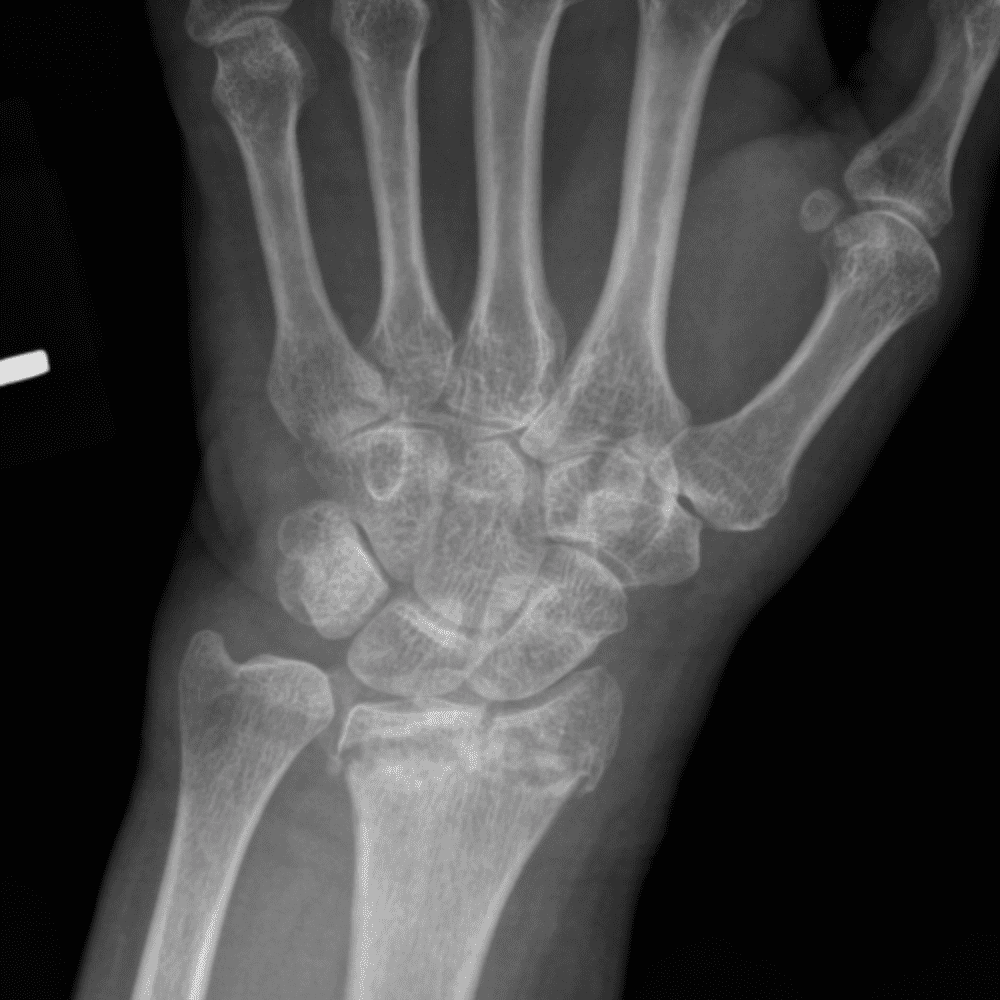

Simuliert den Dienst durch subtile oder schwierige Fälle und einige Normalbefunde.

30 Fälle